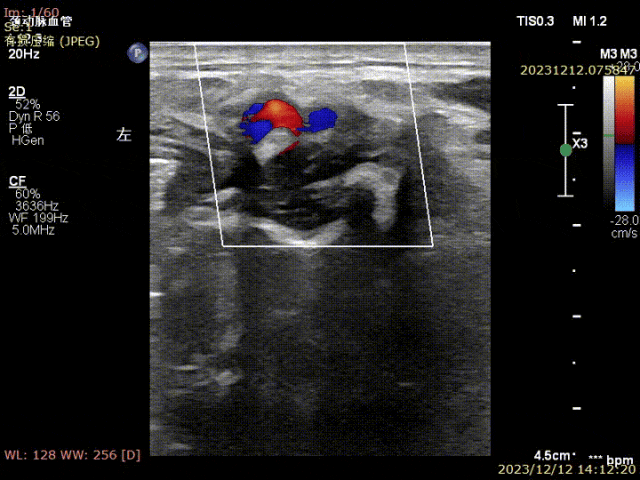

姜坤主任接診后做彩超發(fā)現(xiàn)患者左側(cè)頸總動脈分叉處硬化斑塊鈣化嚴(yán)重,頸內(nèi)動脈起始部重度狹窄(狹窄程度>90%),且斑塊為易損斑塊。

▲患者術(shù)前頸部血管超聲可見頸動脈斑塊,狹窄局部血流速度明顯減慢